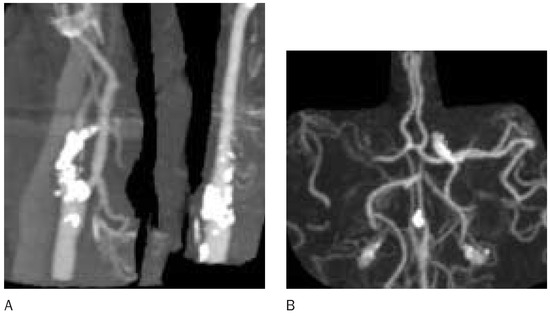

The impact of CT in acute cerebral ischaemia

by Rüdiger von Kummer

Swiss Arch. Neurol. Psychiatry Psychother. 2004, 155(7), 315; https://doi.org/10.4414/sanp.2004.01528 - 1 Jan 2004

Computed tomography (CT) including CT perfusion imaging and CT angiography has the capacity to assess stroke pathology on a functional and morphological level and can thus provide important information about patients with acute stroke. It excludes brain haemorrhage, assesses the extent of perfusion [...] Read more.

Computed tomography (CT) including CT perfusion imaging and CT angiography has the capacity to assess stroke pathology on a functional and morphological level and can thus provide important information about patients with acute stroke. It excludes brain haemorrhage, assesses the extent of perfusion deficit, the extent of ischaemic damage, and the site and type of arterial obstruction. In patients with transient or mild symptoms, the assessment of vascular pathology and consecutive haemodynamic impairment is most important to guide treatment that will prevent disabling stroke. In patients with completed stroke, the early assessment of ischaemic damage is most important. Ischaemic brain tissue below the blood flow level of structural integrity takes up water immediately that causes a decrease in X-ray attenuation. Computed tomography has thus the specific advantage to identify the brain tissue that is irreversibly injured. If CT can exclude major ischaemic damage in acute stroke patients, reperfusion strategies may rescue brain function even after accepted therapeutic time windows. Full article